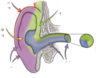

what are the two parts of the temporal bone?

petrous and squamous

what does the IAM contain?

CN7

CN8

labyrinthine artery and vein

what fits into the oval window?

base of stapes

what joints do auditory ossicles articulate via?

synovial joints

what are the two parts of CN8?

cochlear and vestibular nerves

where is the otic capsule?

temporal bone